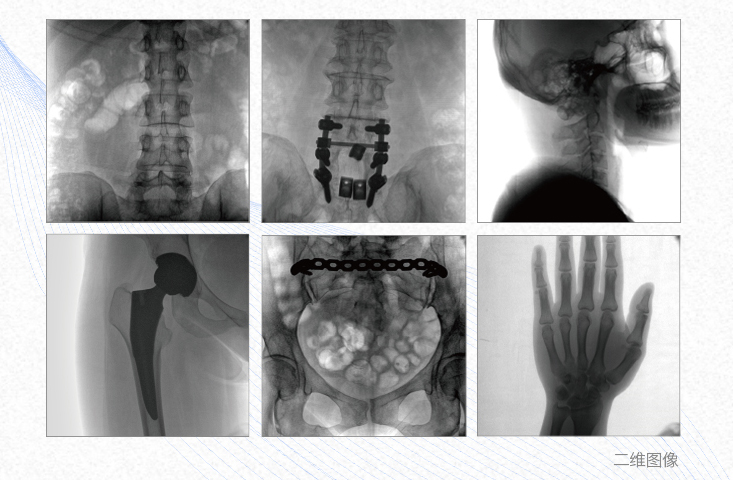

一、平板3DC形臂臨床應用廣泛

1、脊柱外科

有效重建復雜的脊柱三維模型,提供準確的二維、三維圖像,提高螺釘植入的準確性,縮短手術時間,減少并發癥的概率,降低輻射的攝入。

2、創傷外科

例如骨盆骨折內固定術,可術中三維重建髖臼關節面,準確定位并植入螺釘,有效縮短螺釘植入的時間和透視暴露時間,減少術中及術后并發癥發生的概率。

3、關節外科

主要應用于肩關節、肘關節、髖關節、膝關節的關節置換及解剖復位的定位。它可以準確地置入假體,減少輻射時間,降低輻射劑量。

4、截骨矯形外科

例如治療先天性脊柱側后凸畸形,可有效引導術者植入后路螺釘并切除半錐體,達到滿意的截骨矯正效果。